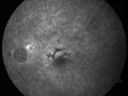

79-year-old woman was seen in the office on 12/22/2009. She has noticed, since the YAG capsulotomy in November of 2009, distortion in the right eye. Part of what she saw were fluffy blue clouds but sometimes there are gray clouds and then she notices that lines are wavy. She does not notice it as much on the Amsler grid as she does on her blinds. This is all in the right eye. The left eye continues to see fine. She does have health problems, including atrial fibrillation for which she takes Coumadin. She also notices pain around the right eye when she bends down VISUAL ACUITY: Vision OD is 20/30, OS is 20/20. IOP: OD 14, OS 13. AMSLER GRID: Right eye has central metamorphopsia. The left eye is normal. SLIT LAMP EXAM: She does have a posterior chamber intraocular lens in good position in both eyes with open capsules with 2+ vitreous debris. EXTENDED OPHTHALMOSCOPY: OD: Vertical C/D ratio is 0.4. There is no posterior vitreous separation. There are hyperpigmented spots superior to the fovea. The fovea is slightly atrophic. OS: Vertical C/D ratio is 0.4. There is no posterior vitreous separation. There are hyperpigmented spots primarily superior to the fovea. There is no intraretinal or subretinal fluid. OCT SCAN: The OCT scan confirms both macula to be dry. PHOTOGRAPHS: Photos confirm clinical findings. FLUORESCEIN ANGIOGRAPHY: There is increase in hyperfluorescence and hypofluorescence in the macula of both eyes. In the right eye there is substantially more hyperfluorescence centrally where the atrophy is. IMPRESSION: 1. NONGEOGRAPHIC PIGMENTED EPITHELIAL ATROPHY – RIGHT EYE 2. PATTERN DYSTROPHY-TYPE MACULAR DEGENERATION – BOTH EYES 3. RECENT AMSLER GRID CHANGE – RIGHT EYE 4. PAIN AROUND RIGHT EYE DISCUSSION: I explained to the patient that both maculae have pattern dystrophy-type dry age-related macular degeneration. I do not see any sign of bleeding or fluid or anything acute that needs attention.

Patterned Pigment Dystrophy of the Fovea 79 YO Woman VA 20/20 Right 20/30 Left1146 views00000